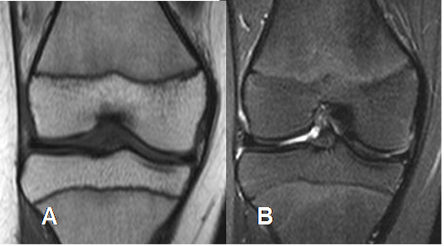

Fig 4 B. Medula ósea en niño normal

A: RM coronal en T1 y B: RM coronal en STIR. Reconversión, con presencia de medula ósea grasa, en la epífisis distal del fémur y proximal de la tibia y roja en ambas metafisis.